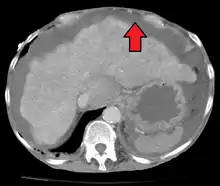

Ultrasound investigation is often performed prior to attempts to remove fluid from the abdomen. This may reveal the size and shape of the abdominal organs, and Doppler studies may show the direction of flow in the portal vein, as well as detecting Budd-Chiari syndrome (thrombosis of the hepatic vein) and portal vein thrombosis. Additionally, the sonographer can make an estimation of the amount of ascitic fluid, and difficult-to-drain ascites may be drained under ultrasound guidance. An abdominal CT scan is a more accurate alternate to reveal abdominal organ structure and morphology.[11]